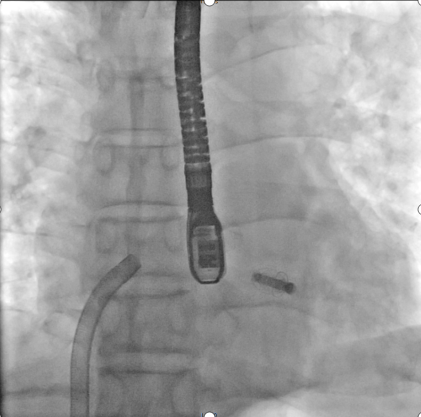

解离后DSA下夹合器形态